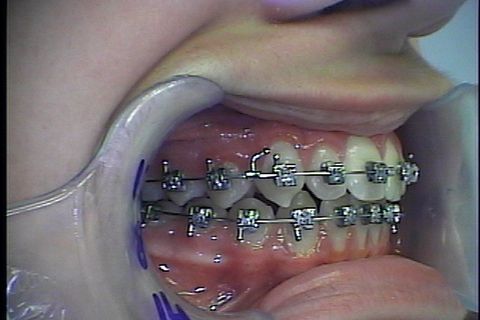

Montagem de fixo

Uso do Twin Force por aproximadamente 3 meses

Twin Force